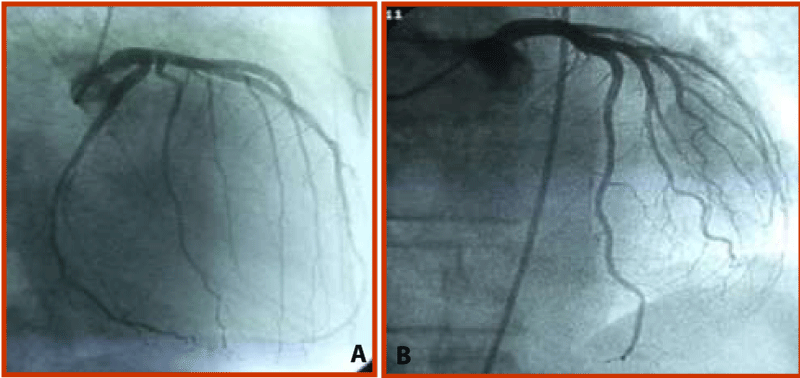

Figure 2:

Fistula disappeared completely after graft stent deployment in proximal LCX segment.